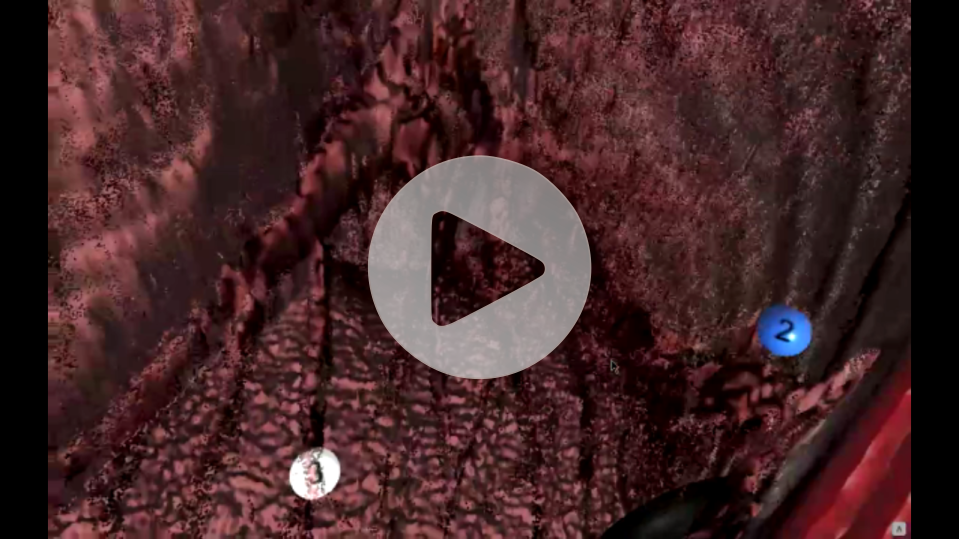

Preview of CT images from

brand new perspective

Profesional tool for doctors witch allowing analizing rentgen image analizing in VR

A modern program for analizing images from the tomograph

Thanks to our program, you will be able to manage lists of your patients in a quick and organized manner, saving time and more efficiently analyzing images from a computer tomograph or magnetic resonance imaging. The application allows you to load photos into the Virtual Reality environment, giving you the opportunity to view and analyze them in a new, unconventional way. Photos displayed in the form of 3D models can be freely rotated and viewed from different angles.